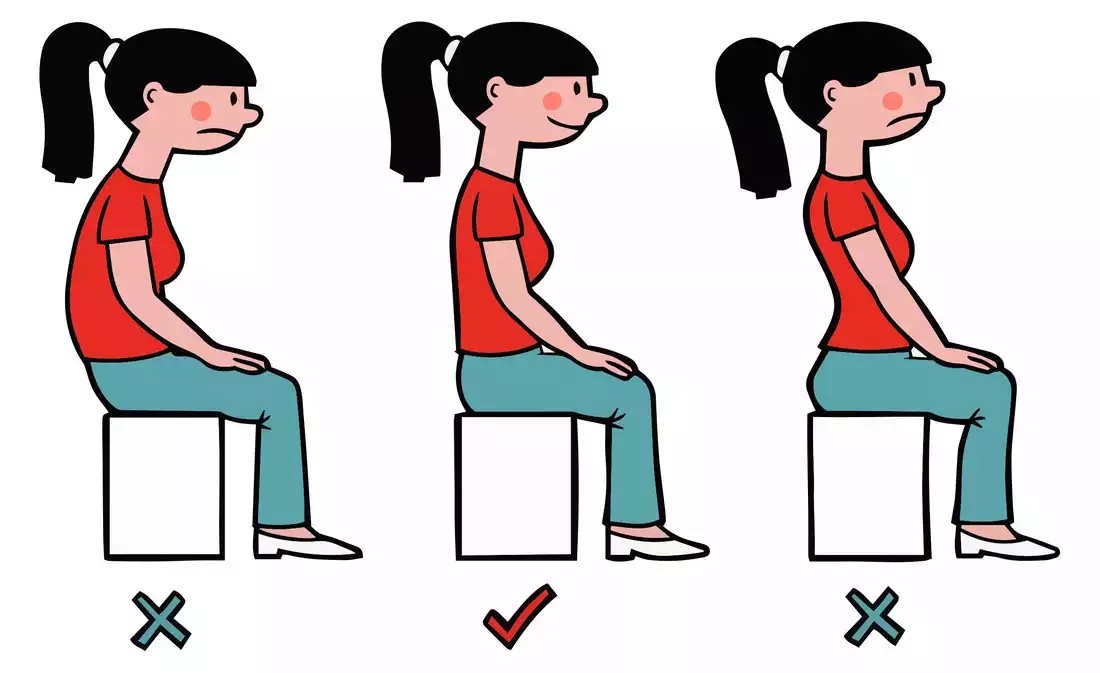

5) الجلوس الخاطئ لفترات طويلة

جلوس الطفل منحنٍ على المكتب أو الهاتف لساعات طويلة يضيف ضغطًا غير متوازن على العمود الفقري، مما قد يسرّع تفاقم الانحناء.

كيف تتجنبيه؟

كرسي يدعم أسفل الظهر.

مكتب مناسب لطول الطفل.

تذكير الطفل بالوقوف والمشي كل 30–45 دقيقة.

تجنب الجلوس على السرير للدراسة أو استخدام الهاتف.